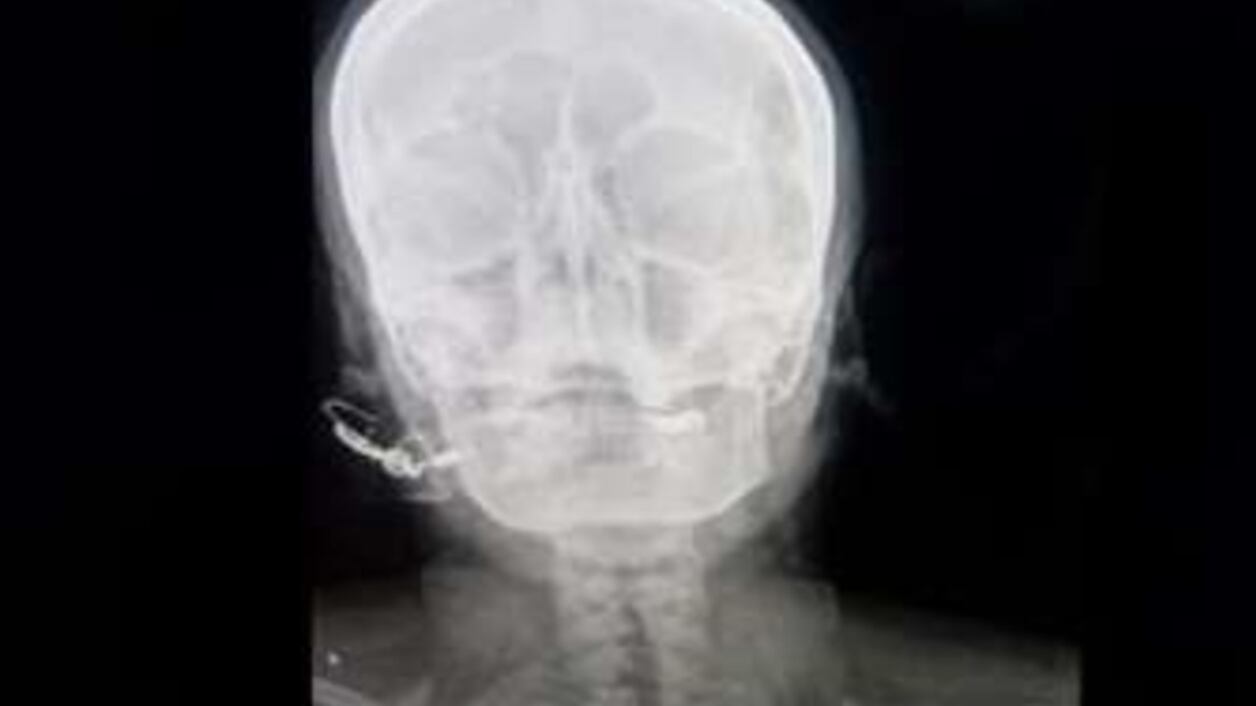

“Estaba totalmente consciente, pero sufría mucho”, señaló el médico. Una radiografía reveló que el clavo había penetrado cinco centímetros en su cráneo, sin llegar al cerebro. La mujer, quien es madre de tres hijas, aseguró estar esperando un cuarto hijo.